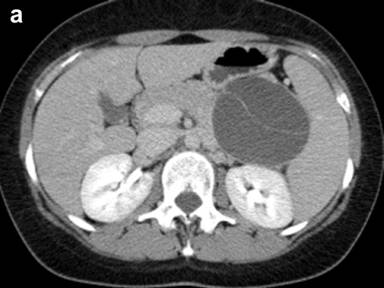

Abdominal US revealed an 8 cm anechogenic mass in the pancreatic tail. Abdominal CT scan was performed using a multi-detector 64 slices CT scanner (Aquilion, Toshiba, Tochigi, Japan) to confirm US findings; unenhanced CT scans showed a well-circumscribed cystic lesion, measuring 8x10 cm in pancreatic tail, with homogeneous low density; an internal this septum was present within the lesions. A contrast-enhanced acquisition was subsequently performed after i.v. bolus (3 mL/sec) injection of 120 mL of a non ionic iodinated contrast agent (Ultravist 370 mgI/mL, Bayer-Shering Pharma, Berlin, Germany) with a scan delay of 120 seconds; an automated dose modulation was used; the cyst wall and the internal septum showed a slight contrast enhancement (Figure 1); the stomach, spleen and left kidney were displaced by the mass. Further diagnostic investigation included a MR scan that was carried out using a 3T MRI (Gyroscan, Philips, Eindhoven, Germany) acquiring axial and coronal T1- and T2-weighted images with and without fat saturation integrated with MRCP T2-weighted hydro-cholangiographic sequences. In particular, the lesion was hyperintense on T2-weighted MR images (Figure 2) and homogeneously hypointense on the pre-contrast T1-weighted MR images showing a mild rim of enhancement after intravenous contrast administration (gadolinium diethylenetriamine pentaacetic-acid) in a volume of 20 mL with 2 mL/s) while maintaining the hypointensity of the central core constant; an internal septum of slight hyperintensity was present within the lesion, that was divided in two parts (Figure 3); MR cholangiopancreatography showed no communication between the lesion and the main pancreatic duct (Figure 4).

Figure 1. CT scan showed an 8 cm thin-walled, non contrast-enhancing cystic lesion in the pancreatic tail with a hyperdense internal septum; axial (a.) and coronal MPR reconstruction (b.) views. |

The macroscopic characteristics of true cyst can be well demonstrates on US, CT and MRI images and allow a differential diagnosis with other cystic lesion of the pancreas [19]. In particular, CT and MRI showed in our case a well defined round mass, thin walled with an internal septum that showed a mild rim of enhancement after intravenous contrast administration; both on CT and MRI there was no solid component or central-cyst wall calcification. In this regard, the correct preoperative differential diagnosis based on imaging findings is a crucial point to select the most appropriate treatment, but it remains a very difficult issue; in particular, a true cyst of the pancreas should be differentiated, mainly, from neoplastic or non-neoplastic cysts. From a radiologic point of view an unilocular macrocystic lesion is indicative of pseudocyst in patient with a history of pancreatitis and/or serum amylase increase or for a true pancreatic cyst; conversely, the presence of the internal septum, is suggestive of a neoplastic nature in particular of intra-papillary mucinous neoplasm, when there is communication between the cyst and the main pancreatic duct, or mucinous cystadenoma [19]. In our case, on the basis of the sex and age, as well as the morphological and imaging findings, the hypothesis of mucinous cystadenoma of the pancreatic was made, but, a true pancreatic cyst was histologically demonstrated; however, the evaluation of the content of the cyst by fine needle aspiration was not available since it was not performed.